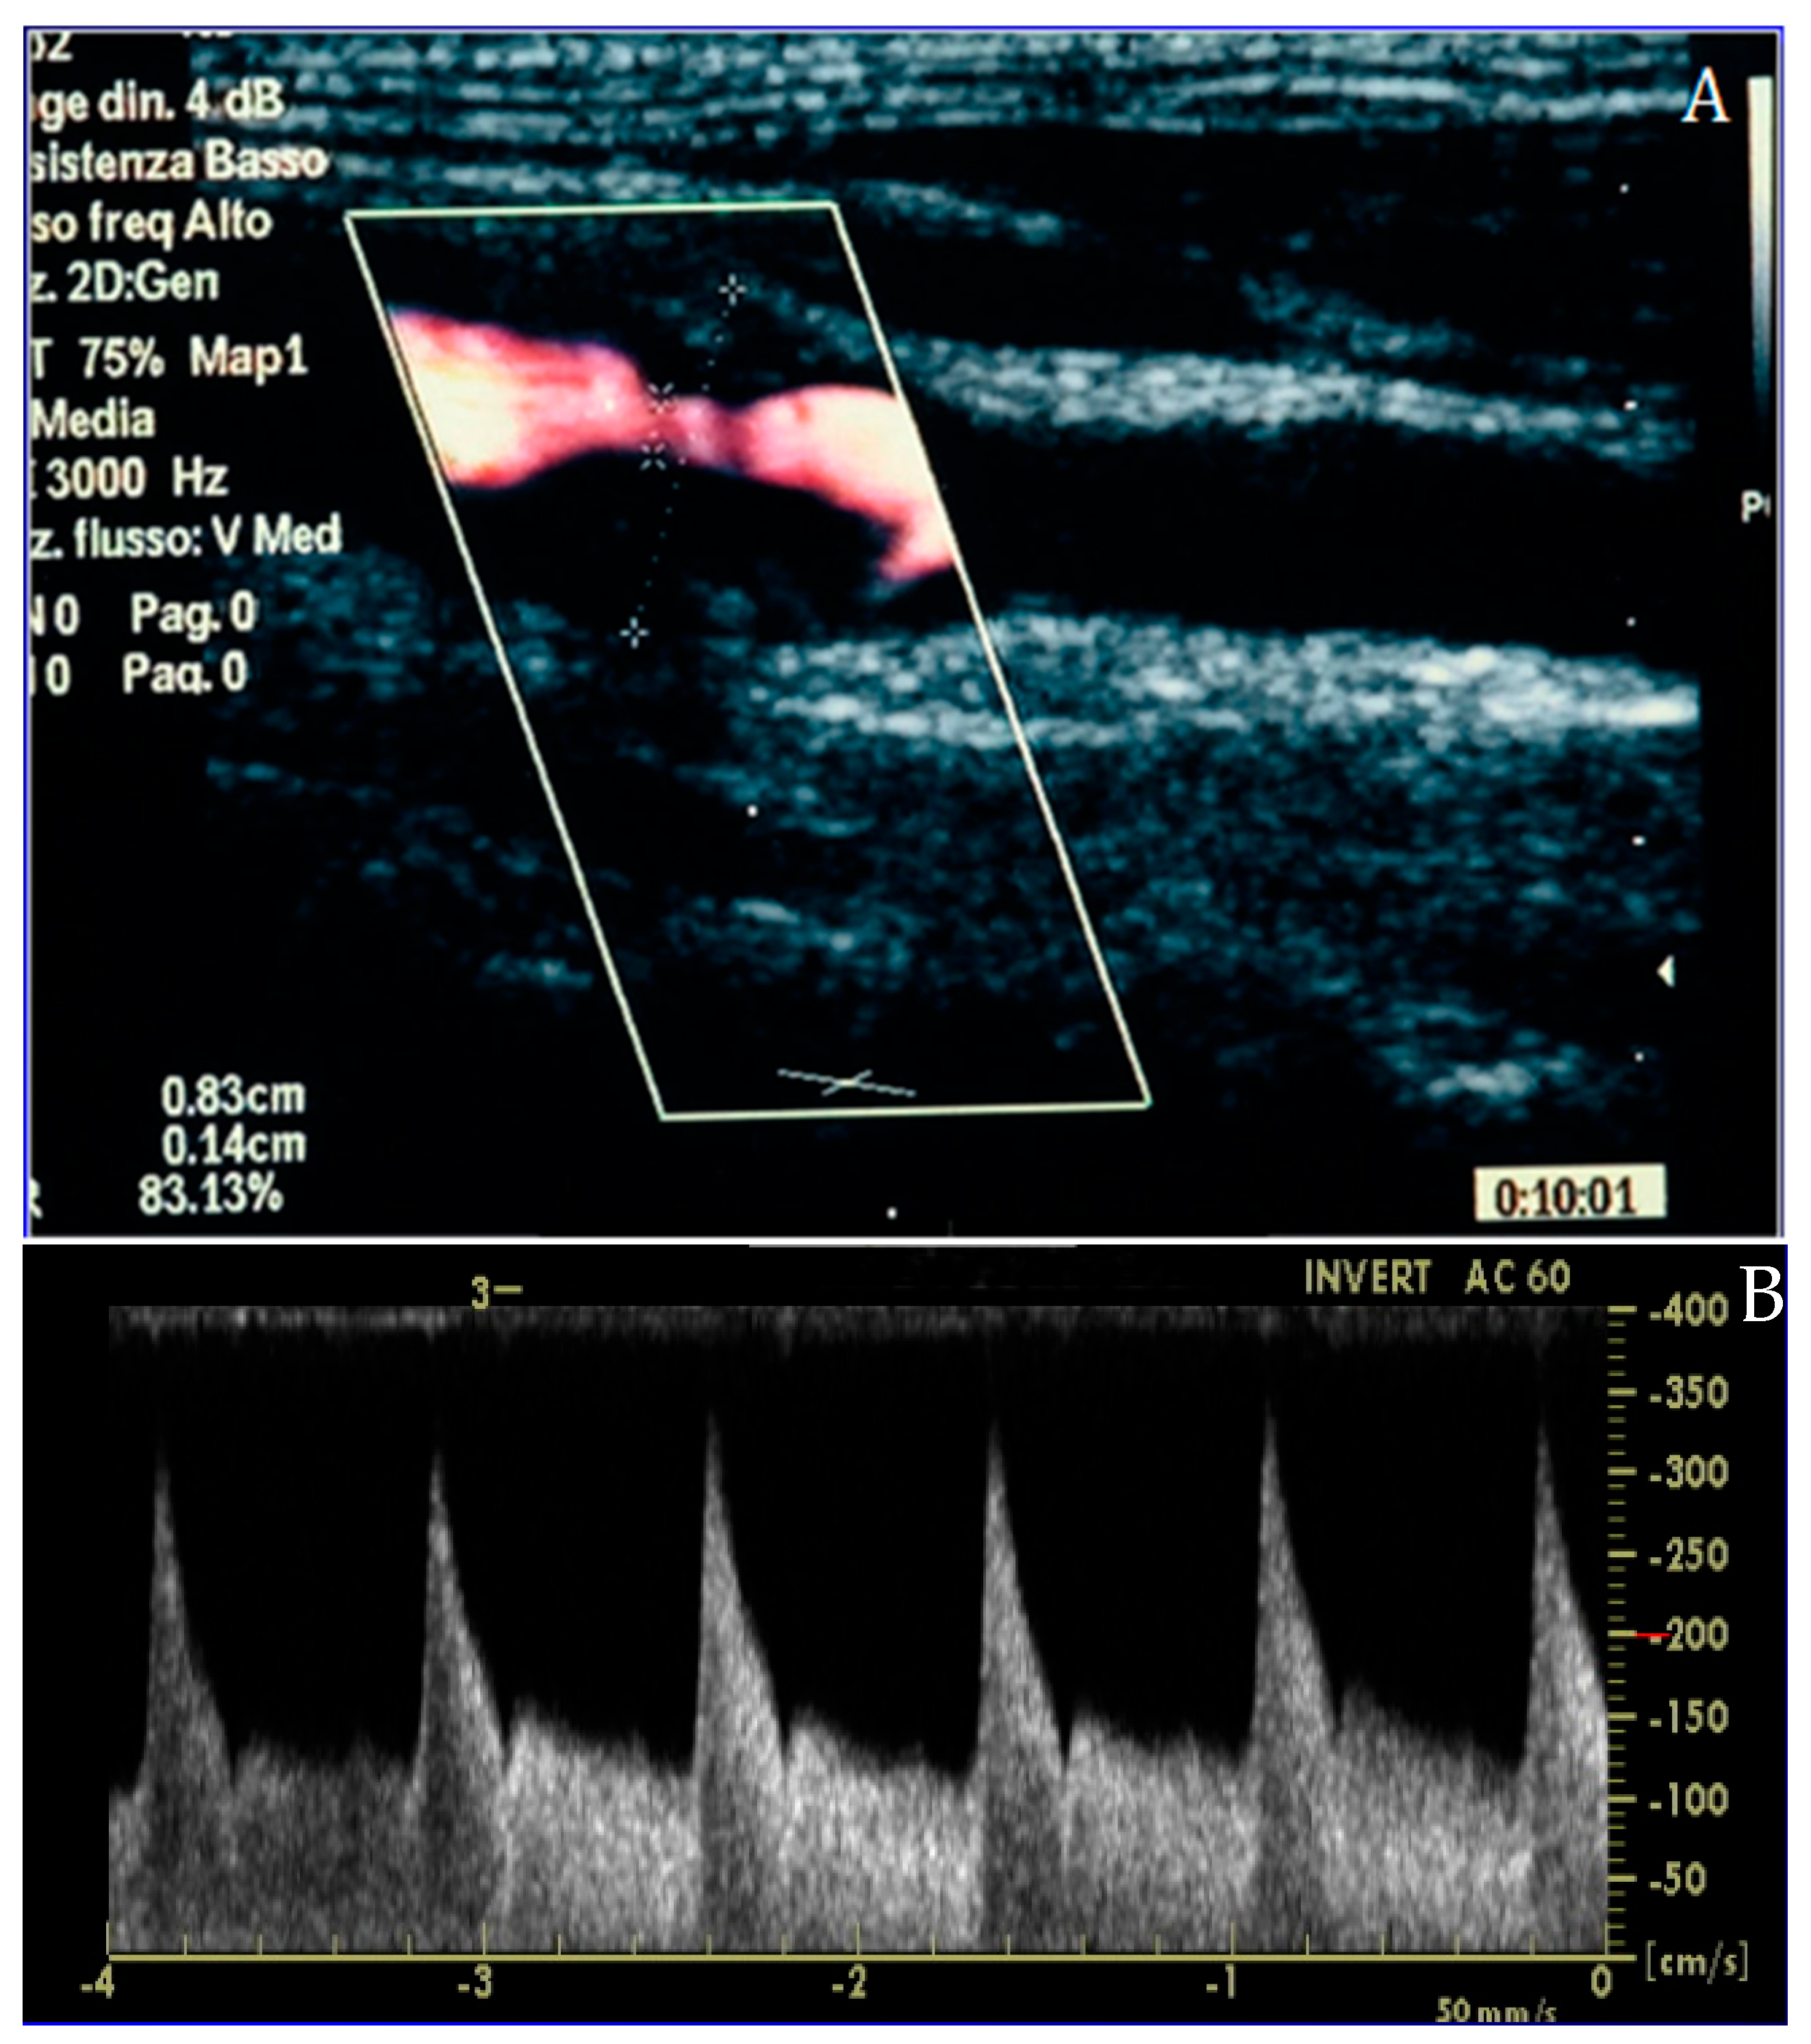

Figure 2.

Carotid duplex ultrasound representation of a significant lesion of the internal carotid artery in long-axis (A) and Doppler assessment (B), confirming the effective flow acceleration across the plaque.